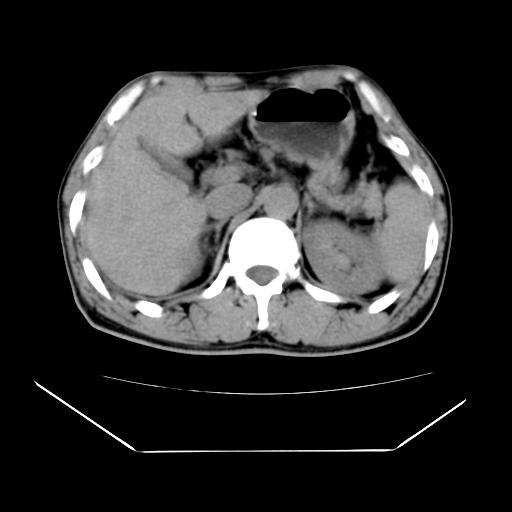

男性,55岁,外院体检afp明显升高,但b超未发现异常,否认乙肝病史。来我院ct增强。有延时扫描。

左肾囊肿.右肺中叶内侧段钙化灶.慢性胆囊炎.

肝脏右叶动脉期可见低密度影,至延迟期被充填,考虑血管瘤可能性大。

肝右叶病灶

不排除肝右叶肝癌可能。

如果这个是癌灶的话则下腔静脉有瘤栓可能

肝6段血管瘤

血管瘤可能性大。

考虑肝右静脉影。